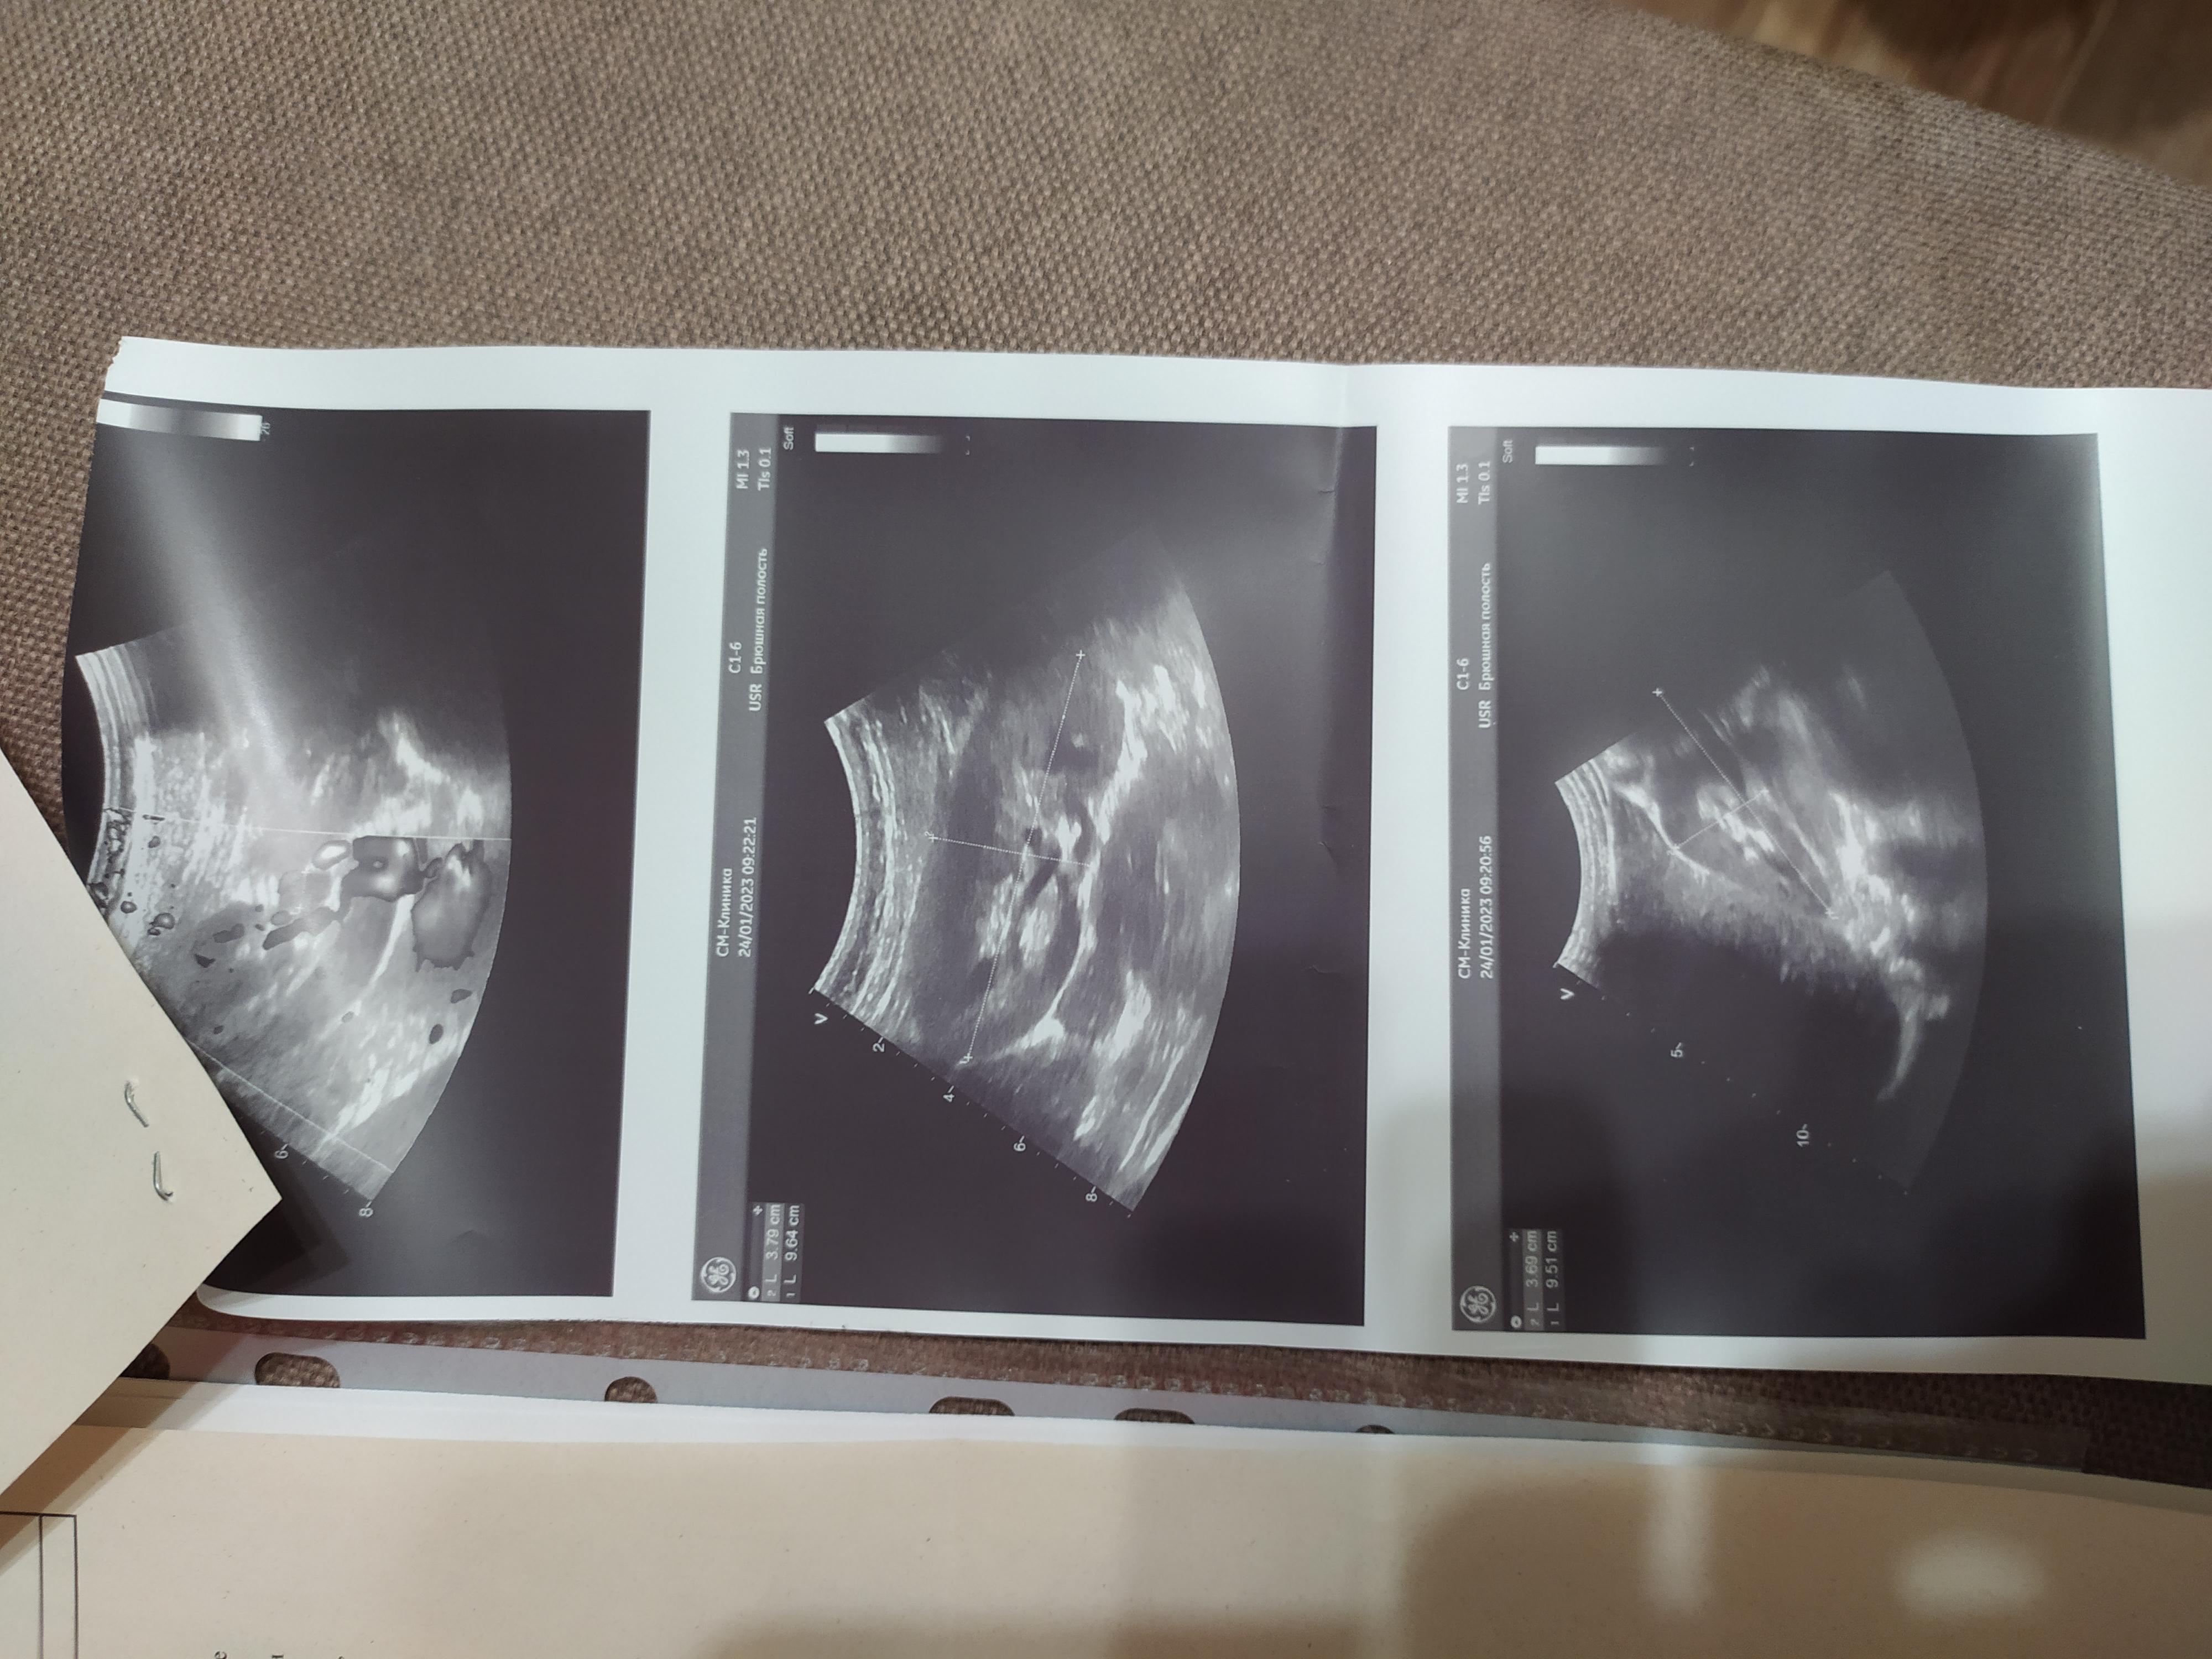

Добрый день! Прошу проконсультировать по поводу анализа мочи и УЗИ. В анализе мочи повышены соли и эритроциты, УЗИ показало расширение лоханки. Чувствую себя нормально, жалоб нет. В детстве переболела пиелонефритом. Результаты анализов прикладываю. Спасибо.